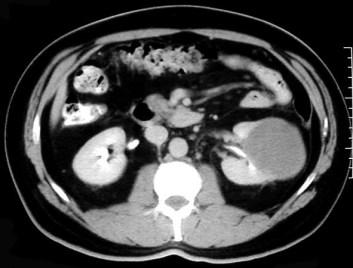

SIGNO VESICAL

Signo visible en la radiografía simple de abdomen que permite diferenciar entre una vejiga muy distendida (globo vesical) y una masa pélvica de otro origen. La distensión de la vejiga se ve como una densidad homogénea redondeada u oval de borde superior definido, que ocupa la pelvis obliterando las zonas laterales de la pelvis y desplazando lateralmente el ciego y el sigma.

Las flechas negras marcan el borde superior vesical bien definido. Obsérvese el borramiento de planos grasos en la pelvis (flecha naranja), el desplazamiento lateral del ciego (flecha blanca) y superior del sigma (flecha roja).